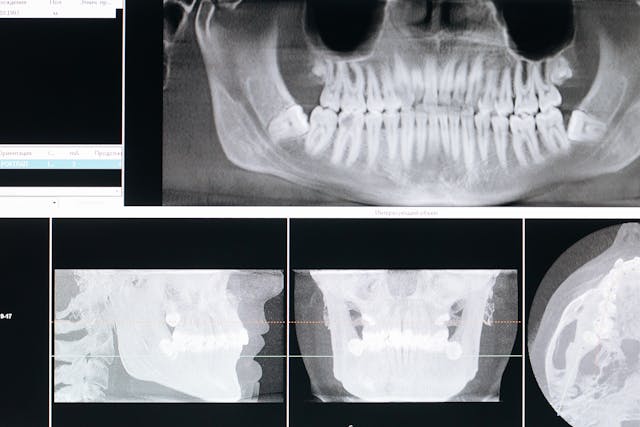

14 marca, 2026Tomografia komputerowa zębów to badanie obrazowe stosowane w diagnostyce stomatologicznej. Pozwala dokładnie ocenić struktury kostne, korzenie zębów oraz przebieg nerwów. Ze względu na wykorzystanie promieniowania pojawia się pytanie o częstotliwość wykonywania badania. W tym przypadku decydują konkretne wskazania medyczne oraz zasady bezpieczeństwa.

Tomografia stożkowa CBCT stosowana w stomatologii generuje niższą dawkę promieniowania niż klasyczna tomografia komputerowa, ale wyższą niż standardowe zdjęcie RTG.